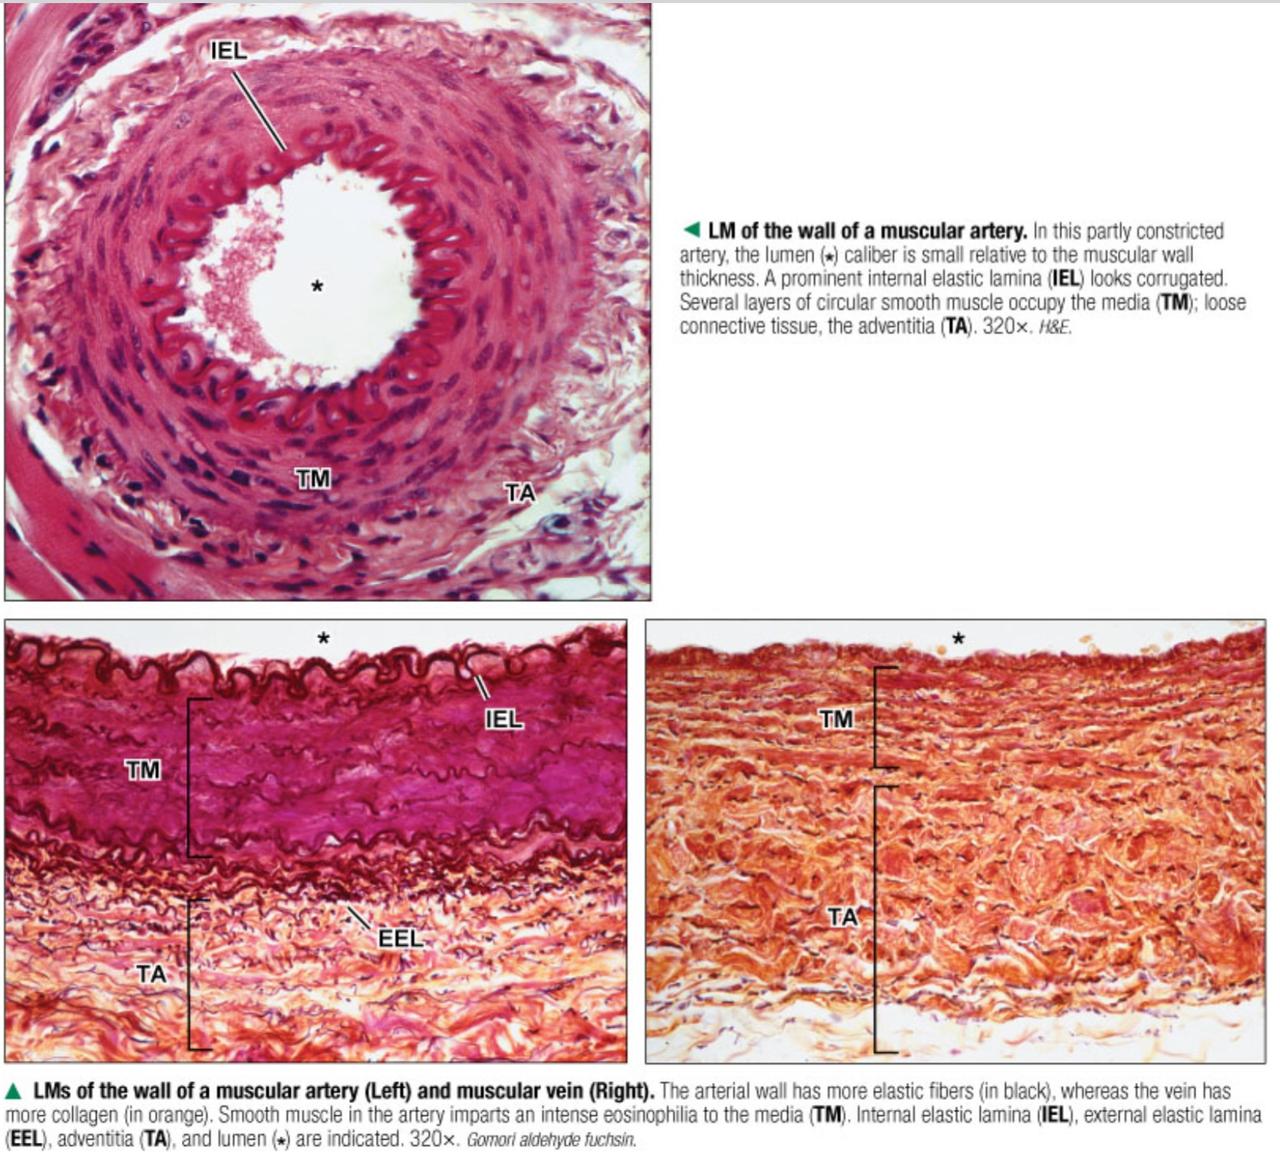

Fig 3.44: Opbouw van verschillende types arterien

A arteriool (< 500 um)

B musculaire arterie (rode kleur)

C elastische arterie (gele kleur, bv. aorta)

-

tunica intima

lamina elastica interna -

tunica media

gladde spiercellen elastinevezels

lamina elastica externa -

tunica adventitia

|